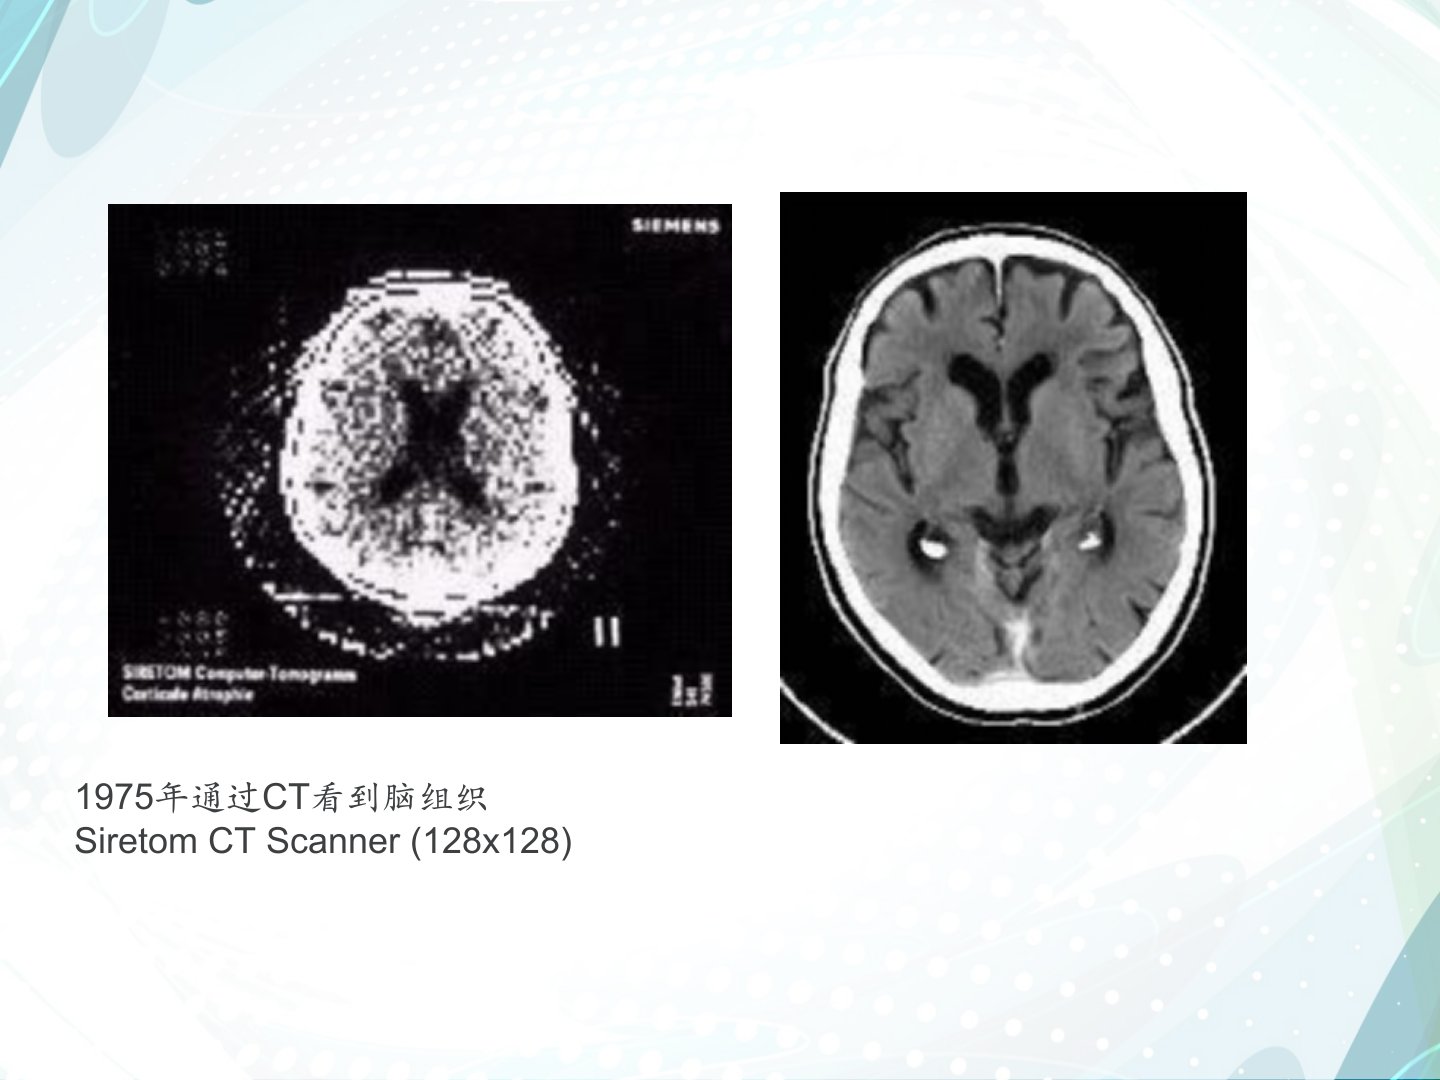

头颅CT读片技巧省院神内常规检查,由于CT的密度分辨率高,对软组织的显示优于常规X线检查。增强CT扫描检查,除能分辨血管的解剖结构外,还能观察血管与病灶之间关系,病灶部位的血供情况和血液动力学变化。因为轻微活动会造成伪影,使图像难以诊断,除取得患者合作外,对难于合作的患者或儿童需给予镇静剂或麻醉。CT临床应用1975年通过CT看到脑组织SiretomCTScanner(128x128)CT扫描基线扫描基线听眉线:外眶上嵴到耳屏上缘听眦线:外眼眦到耳屏上缘头听眶线:外眶下嵴到耳屏下缘颅脑扫描一般以听眶下线为基线向上扫至头顶层厚:8-10mm,层距:10mm1.冠状面2.矢状面3.横断面CT扫描层...